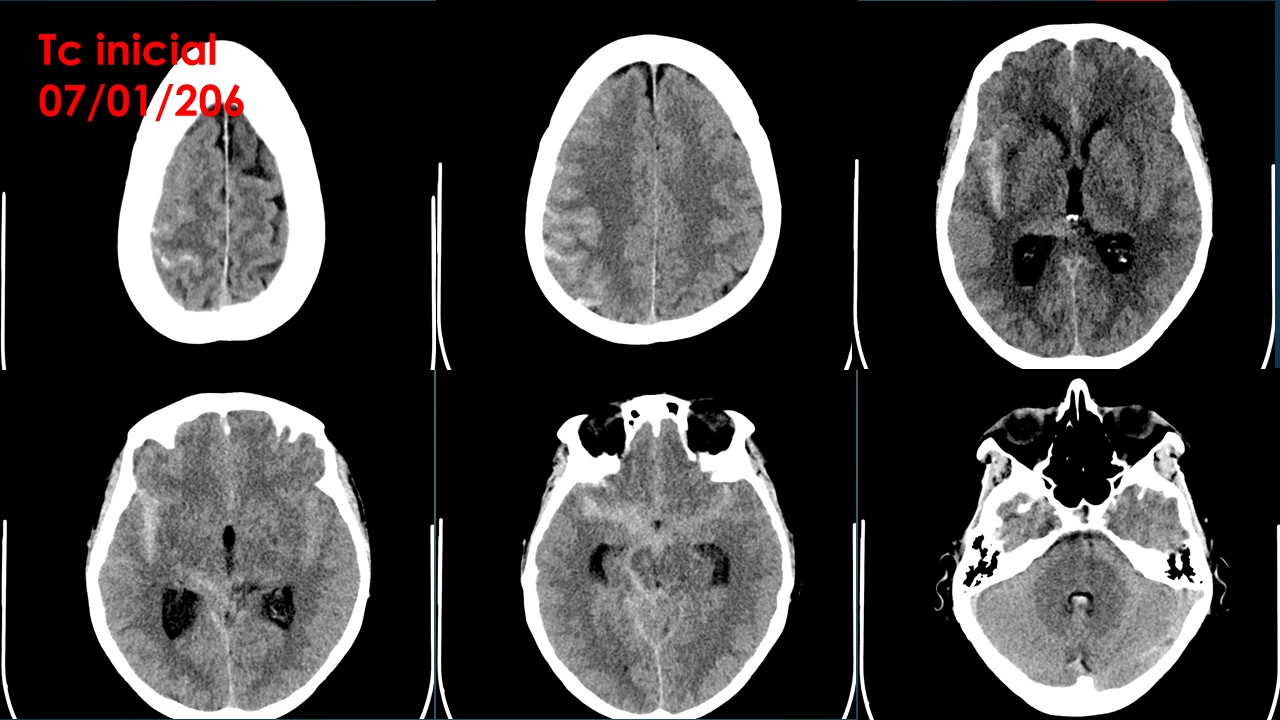

TC CRANEAL SIN CONTRASTE

Extensa hemorragia subaracnoidea aguda con afectación de las cisternas peritronculares, cisura Silviana bilateral, de predomino derecho y los surcos de la convexidad predominantemente derechos. Se asocia a contaminación hemática tetraventricular con leve aumento de tamaño del sistema ventricular.

Cisternas de la base y surcos bilaterales de predominio derecho ocupados en relación a edema cerebral.

Estructuras de la línea media centradas.